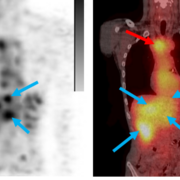

Radioligands give Molecular Partners new momentum in a market already at full speed

Latest NewsThe Zurich-based developer is increasingly focusing its pipeline on radiopharmaceutical cancer therapies. A recent development agreement with isotope specialist Eckert & Ziegler marks another step in that direction. The collaboration aims to develop and manufacture so-called Radio-DARPin therapeutics, in which targeted protein molecules deliver radioactive isotopes directly to tumours. Early clinical data on the DARPin molecules in combination with radioisotopes suggest targeted tumour localisation. Proof of efficacy, however, is still pending.